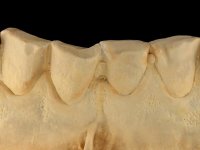

The endocrown should be constructed with a zirconia framework with an ‘intra-root’ and crown components, being this last one veneered with ceramics.

CAD-CAM technology was used to design and construct an endocrown with a zirconia framework veneered with ceramics. The crown was then bonded to the tooth, by using an MDP based adhesive and a dual polymerization composite resin.